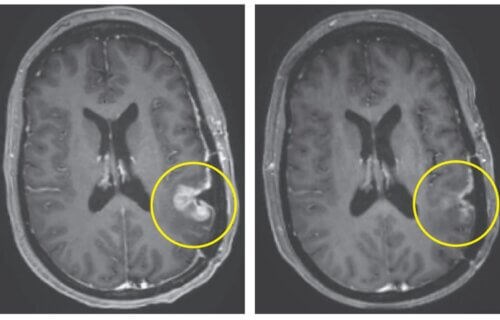

Στη μελέτη, η οποία διήρκησε από τον Μάρτιο έως τον Ιούλιο του 2023, συμμετείχαν μόνο τρεις ασθενείς. Οι ερευνητές συνέλεξαν τα Τ κύτταρα των ασθενών τα οποία μετέτρεψαν σε νέα κύτταρα CAR-TEAM και στη συνέχεια τα έγχυσαν ξανά σε κάθε ασθενή. Αν και σχεδόν όλοι οι συμμετέχοντες εμφάνισαν πυρετό και αλλαγές στην ψυχική τους κατάσταση λίγο μετά την έγχυση, δεν ανέφεραν άλλες παρενέργειες. Είναι αξιοσημείωτο ότι λίγες μέρες μετά από μία μόνο θεραπεία, οι όγκοι τους συρρικνώθηκαν σημαντικά, με έναν ασθενή να επιτυγχάνει σχεδόν πλήρη υποχώρηση του όγκου μέσα σε πέντε ημέρες.